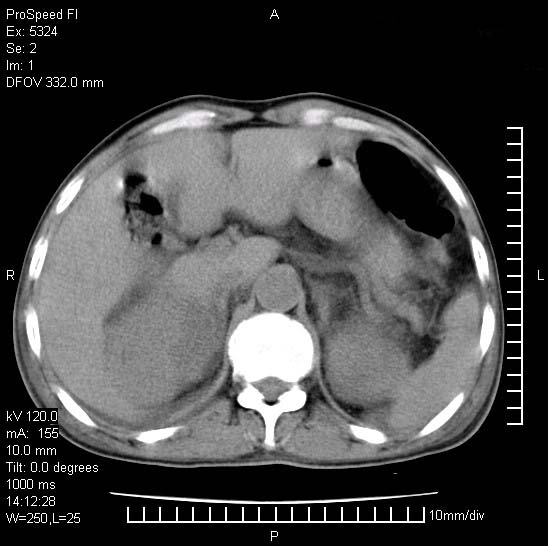

患者阴囊肿大14月,腰痛2个月,咳嗽,咳痰1周,患者现在肾功异常,做增强有些担心,我们用的是欧乃派克.

右侧肾癌伴腹膜后淋巴结转移!

右侧肾癌后腹膜转移,腹腔少量积液

腹膜后淋巴结肿大包饶腔静脉,双肾病变,建议增强

双肾均有软组织密度舯物,腹膜后淋巴结肿大包饶腔静脉------考虑为恶性占位病变,转移瘤可能。

左肾也有问题呀///

支持:双肾均见软组织密度肿块影,腹膜后淋巴结肿大包绕腔静脉------考虑为恶性占位病变,转移瘤可能。

1)考虑双肾恶性肿瘤(肾癌?)。2)腹膜后淋巴结肿大,多为肿瘤转移所致。

腹腔积液,双肾均有稍高密度肿块,主动脉旁广泛淋巴结肿大,融合,无显著肿块坏死征像,多考虑淋巴瘤累及双肾,不排除肾癌伴转移(肾癌这么大应该较多坏死了),另阴囊肿大,不知是实质肿大还是阴囊积液,如是是积液,多为腹腔肿块压近睾丸静脉所致,如是是实性的,多为淋巴瘤

1、淋巴瘤,双肾转移瘤;2、双侧肾癌,伴有腹膜后淋巴结转移。

双肾周围及腹膜后改变符合恶性病变,现在关键是要明确阴囊肿大的原因,是否为肿瘤性病变.如阴囊为恶性肿瘤那一切用转移即可解释,如阴囊为水肿改变,那需重新分析检查明确.

双肾均有软组织肿块伴腹膜后淋巴结肿大融合,右侧结肠旁沟积液;考虑恶性肿瘤。转移瘤?淋巴瘤?

阴囊肿大是实质性的么,为什么不扫阴囊,此扫描做的是什么部位,肾脏没包括全,也可以考虑生殖系统肿瘤转移

双肾增大,腹膜后多发肿大淋巴结影.首先考虑淋巴瘤.

双肾增大,结合腹膜后淋巴结肿大,考虑双肾恶性肿瘤并转移可能。

双肾癌并腹膜后淋巴结转移

考虑恶性淋巴瘤侵及双肾,腹膜后淋巴结肿大。